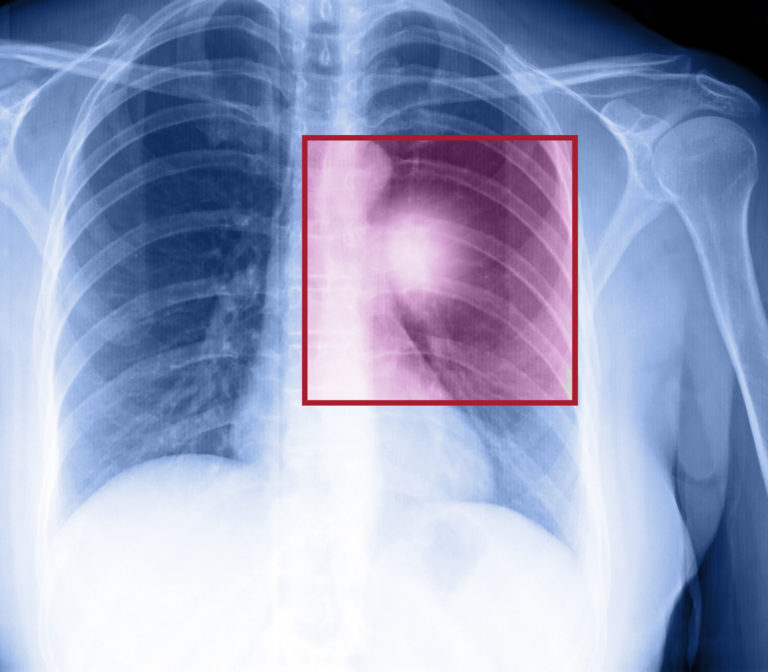

Dr. David Gerber, associate professor of internal medicine and clinical sciences at UT Southwestern Medical Center says, “Many tumors in the lung never cause much symptoms, and that is why, without screening, almost ¾ number of patients have cancer which is too advanced for surgery as it has already spread”. Doctors usually catch the early stage of lung cancer by accident. For example, a doctor might be administering a chest X-ray for a fracture but accidentally catches the growing cancer.

Dr. David Carbone, medical oncologist and director of the Thoracic Oncology Center at The Ohio State University Comprehensive Cancer Center – Arthur G. James Cancer Hospital and Richard J. Solove Research Institute says, “Since there are no nerve endings in the lungs, you can have a lot of tumors growing inside your lungs without you even noticing it. A large number of lung cancer patients are usually diagnosed from different symptoms after the cancer has already spread [metastasis] to various other parts of their body, such as their liver or even spine.”